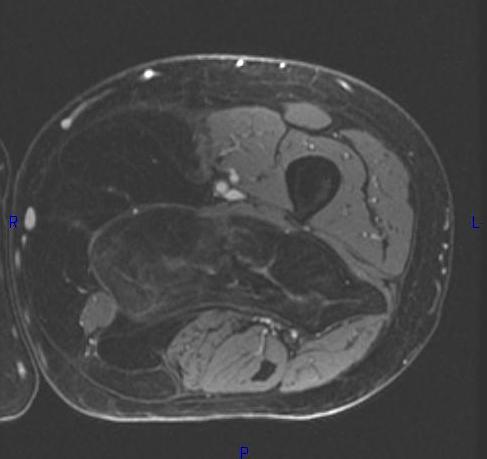

MRI (Fig. 1, 2, 3 and 4)

• Large encapsulated lipomatous mass. (Fig. 1, 2, 3 and 4)

• Nonadipose components; prominent thick septa and focal nodular regions usually less than 2 cm in size. (Fig. 3)

Fig. 2-4 MRI: Coronal T2-weighted fat suppressed (Fig. 2) and Axial T2-weighted FS (Fig. 3) shows low intensity signal isointense with fat. Adypocitic lesion with fatty signal is located in the posterior and medial compartment of the thigh. Thickened septa and nodularity enhances on post contrast images. (Fig. 4)